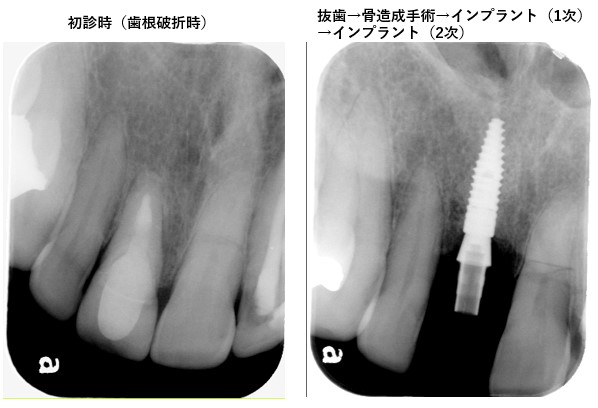

2枚のレントゲン写真を添付します

画像1画像2枚.jpg

結果、炎症により上右1だけでなく両隣の上左1・上右2の歯を支える骨までもが広範囲にわたり消失

・上右1は抜歯半年後に骨造造成手術を経てインプラント実施

(当方としては添付写真の通り、歯を支える骨がごっそり消失したことにより、二次性咬合性外傷と同じような状態になっているのではと考えます。)